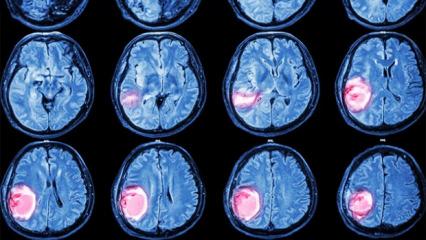

Beyin tümörlerinde 3 kritik sinyal!Beyin tümörlerinde 3 kritik sinyal!